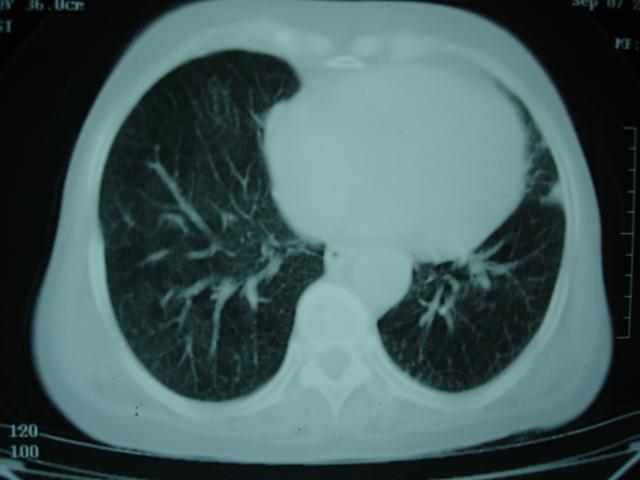

以下是引用卜一在2009-9-7 19:51:00的发言:[br][br] 1 左侧胸内甲状腺占位-多考虑甲状腺腺瘤! 2、左肺门占位-建议增强扫描以便明确性质。 3 慢支并感染! [br]

以下是引用shibing在2009-9-7 20:40:00的发言:[br]左侧胸内甲状腺占位-多考虑甲状腺腺瘤! 2、左肺门占位-建议增强扫描以便明确性质。 3 慢支并感染! [br]